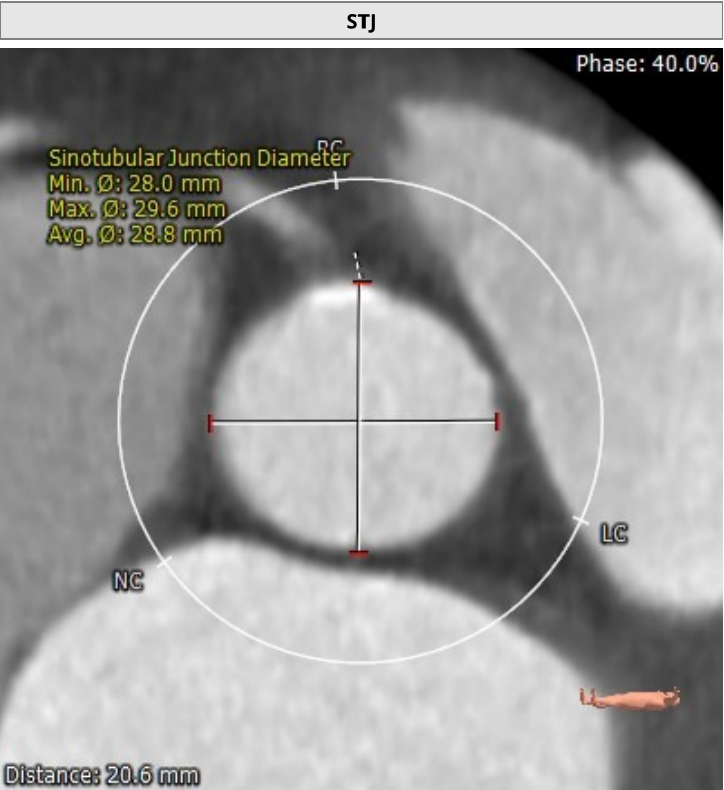

该名患者为Type 0型二叶瓣,右冠窦轻度钙化。瓣环最短径为20.0mm,最长径为27.7mm,平均瓣环直径为23.8mm。升主动脉较宽,平均直径40.5mm。左冠开口高度13.6mm,右冠开口高度16.3mm,冠脉阻塞风险低。外周血管钙化轻,入路情况较佳。FEops分析推荐匹配26mm瓣膜。

窦管交界部

升主动脉